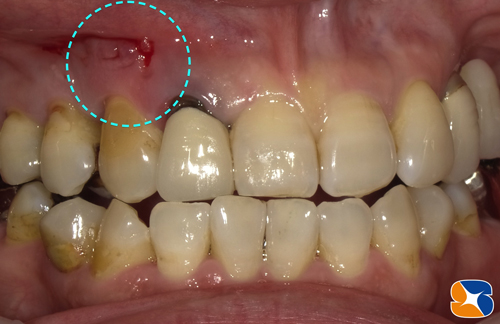

〈手術1〉60代の女性。主訴は「糸切り歯がグラグラしている。歯茎を押すといつも膿みが流れる。何処の医院へ行っても入れ歯か、他の歯を削って4連結のブリッジしかないと言われる。

本当はインプラントを希望してるので、抜くに抜けない。」でした。

歯科用CTで患者様の骨の状態を診断します。糸切り歯(犬歯)のほっぺた側の骨が、全て失われている状態でした。インプラントを断られるのも無理はありません。